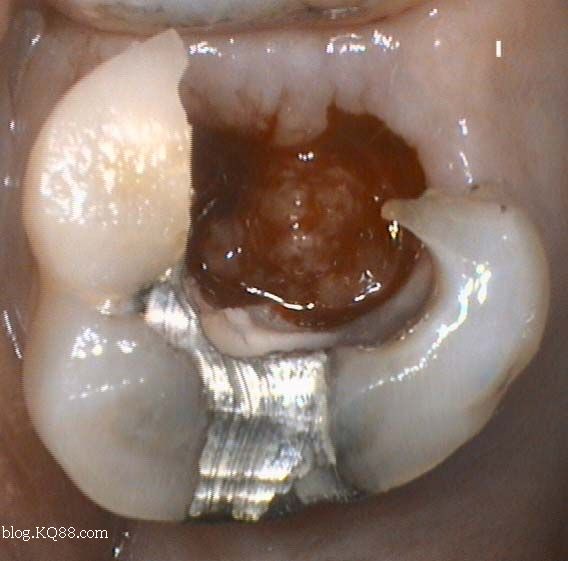

1、口腔鏡檢查:通過口腔鏡檢查,可以清晰地觀察到牙齒表面的牙洞以及牙洞內的情況,醫(yī)生可以判斷牙洞是否已深入牙髓,并評估病情嚴重程度。

2、探診檢查:使用牙科探針檢查牙洞周圍組織的健康狀況,了解牙洞深度及與牙髓的關系。